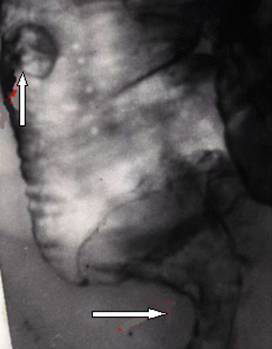

Рак толстой кишки.

Рис. 3. Циркулярный рак прямой кишки (горизонтальная стрелка). «Пограничный» полип дистального отдела сигмовидной кишки (вертикальная стрелка).

Предоставил Дементьев Е.З.

Радиология-практика 2004 2: 48-56